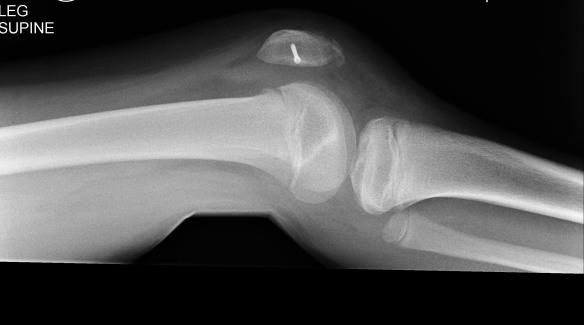

X-ray shows good progress, so time for a new cast and another 4 weeks on crutches.